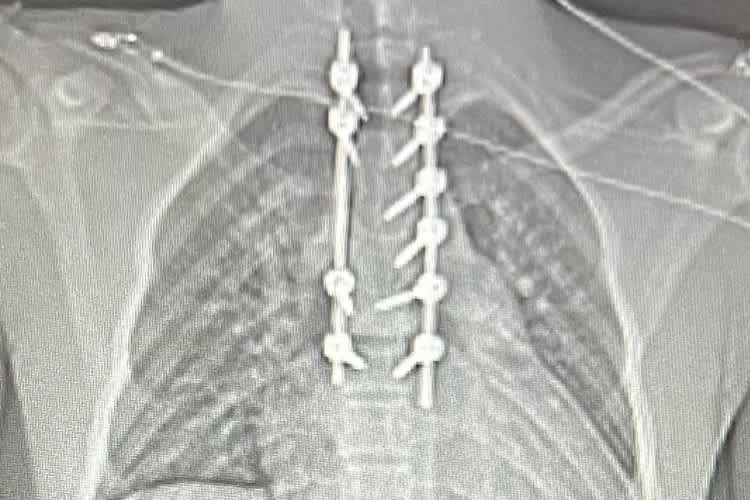

Der beim Hawkstone International schwer verletzte Ashden Barlow wurde erfolgreich operiert. Die gebrochenen und beschädigten Wirbelkörper wurden mit Metallstangen verbunden und fixiert.

Für den Ende Februar beim Vorsaisonrennen Hawkstone International in der 125-Klasse schwer verletzten Briten Ashden Barlow gibt es Hoffnung. Zur Erinnerung: Neben zahlreichen inneren Verletzungen und Blutungen wurden bei dem Crash 8 Wirbel gebrochen oder beschädigt. Das Schlimmste: Der Spinalkanal war betroffen, so dass eine Querschnittslähmung zu befürchten war.

Inzwischen wurden die beschädigten Wirbel im Brustbereich operativ mit Metallstangen und Schrauben fixiert. Ashden hatte nach dem Unfall und später auf der Intensivstation kein Gefühl mehr in der rechten Körperhälfte. Nach vielen Tagen des Bangens kann er sein Bein wieder bewegen. Das bedeutet zwar in Hinblick auf Spätfolgen noch keine Entwarnung, aber es gibt Hoffnungen, dass er wieder in sein normales Leben zurückfinden kann. Dafür drücken wir im Namen aller Leser die Daumen und wünschen von dieser Stelle aus gute Genesung.